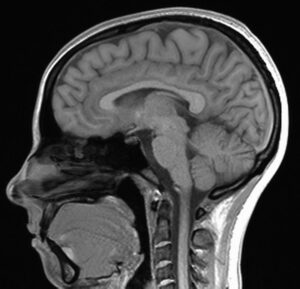

Daniel Foti, associate professor of clinical psychology and neuroscience and behavior, counted on human participants coming to his Psychophysiological Analysis of Cognition, Emotion, and Reward (PACER) lab at Purdue University to participate in studies to measure brain activity through electroencephalography (EEG) and functional magnetic resonance imaging (fMRI).

The data Foti is receiving from these “mail-order” kits has been helpful in continuing his studies on Angelman syndrome and autism spectrum disorder (ASD). The kits increase access for families either unable or unwilling to drive sometimes hours to Foti’s lab. The families can better understand and treat disorders like Angelman syndrome or autism without leaving their home. The EEG equipment is worn by participants and measures brain activity as the participant goes through videos, images and interviews using software on the digital tablets.

COVID-19 temporarily slowed down the lab of Brandon Keehn, associate professor of speech, language and hearing sciences, too. Inside his Attention and Neurodevelopmental Disorders (AtteND) lab, Keehn uses fMRI, EEG and eye-tracking technology to understand attentional strengths and weaknesses in children with ASD.